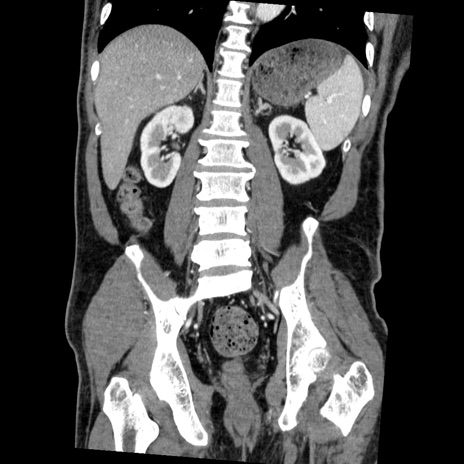

症例22(冠状断像)

【症例】50歳代男性

【主訴】腹痛

【現病歴】AVMからの被殻出血のため回復期リハ病棟入院中。 本日午後3時頃急に下腹部痛が出現した。

【既往歴】AVM、被殻出血、虫垂炎、高血圧

【身体所見】意識晴明、左半身不全麻痺、会話の理解は良好、36.5°C、腹部:膨隆、全体に板状硬、下腹部正中に圧痛点あり、反跳痛-、筋性防御不明、右下腹部にope scar

【データ】WBC 9400、CRP 0.06